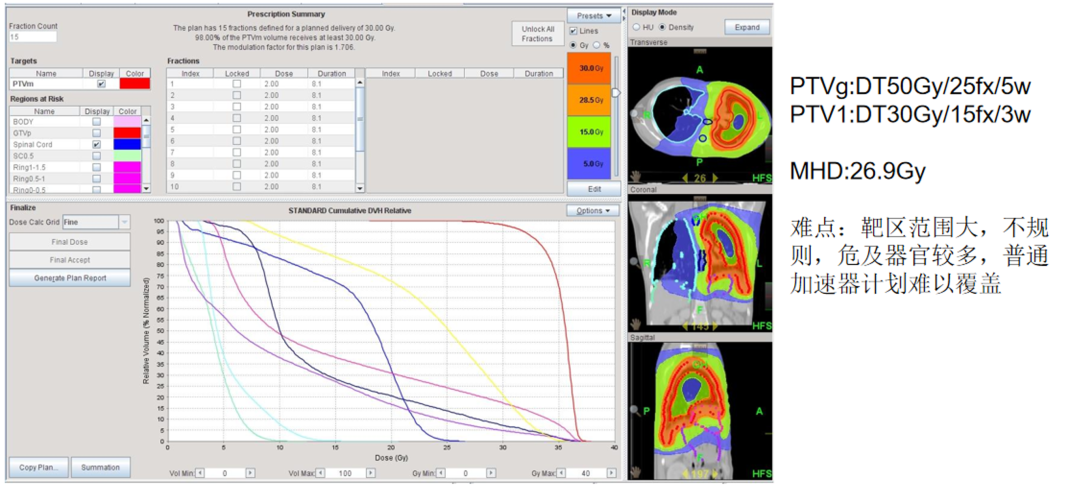

病例2:纵隔横纹肌肉瘤伴肺转移的大范围精准治疗

向先生(化名)在2024年8月确诊为纵隔横纹肌肉瘤,并伴有肺转移。在接受手术治疗和化疗后,针对肺转移瘤及胸膜病灶,他选择了TOMO放疗。

TOMO放疗的照射范围广泛,能够覆盖胸腔内的复杂病灶,实现多靶区同时照射,这对于处理向先生的病情非常有利。通过多叶光栅和螺旋CT扫描技术,TOMO放疗实现了对肿瘤的高精度调强照射,减少了对肺、心脏等敏感器官的损伤,提高了治疗效果。同时,其适应复杂解剖结构的能力,使得TOMO放疗能够处理形状不规则、位置复杂的胸膜病灶,确保治疗的安全性和有效性。

TOMO剂量分布图

治疗前后对比图